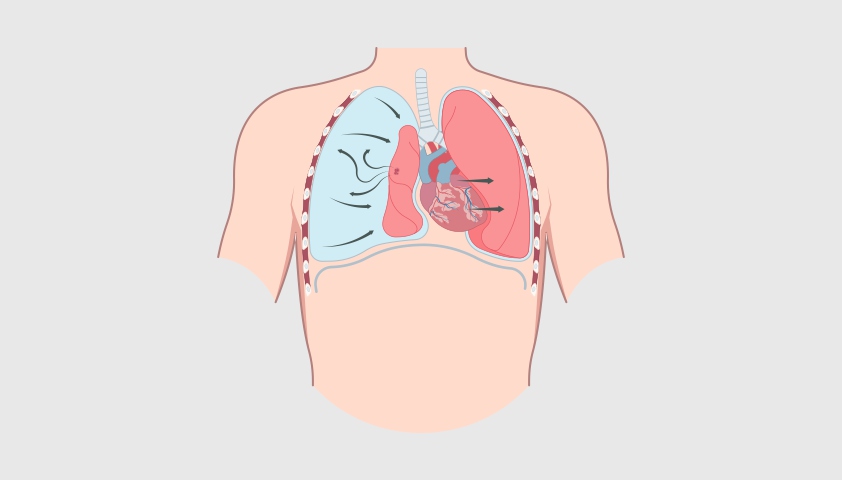

При пневмотораксе воздух проникает в герметичное пространство вокруг лёгкого — плевральную полость. Это приводит к сдавливанию дыхательного органа, из-за чего он не может полностью расправиться при вдохе. В результате нарушается дыхание, а в тяжёлых случаях может возникнуть угроза для жизни.

При пневмотораксе баланс давлений между плевральной полостью и лёгким нарушается — и оно опадает, как сдувшийся шарик

Напряжённый пневмоторакс — самый опасный вид заболевания, когда воздух попадает в грудную полость и нарушает работу не только лёгких, но и сердца, создавая избыточное давление. В результате лёгкое сжимается, сердце и сосуды смещаются, что может привести к жизнеугрожающему состоянию. Без срочной медицинской помощи это может привести к остановке дыхания. Распознать состояние можно по резкой нехватке воздуха, посинению кожи, набуханию вен на шее и резкому падению давления.

Наиболее опасен напряжённый пневмоторакс — состояние, возможное при пневмотораксе любого типа, при котором воздух непрерывно поступает и накапливается под давлением, деформируя лёгкое и смещая сердце.